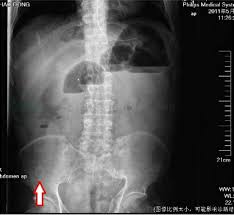

wl大心脏 请问心脏CT如何做增强处理?目前考虑的是尝试各种WWwl大心脏 WL,还有其他好方法吗?wl大心脏 wl大心脏 病例分享:多发结节又是多原发早期肺癌!浸润性也楔切是否真的合适?wl大心脏 當心理學家研發藥物——臺大賴文崧談思覺失調與多重系統退化症wl大心脏 劇烈肚子痛竟然是主動脈剝離wl大心脏 30歲男子脾臟腫大近2倍險破裂腹腔鏡微創手術開刀切除wl大心脏 wl大心脏 wl大心脏 wl大心脏 wl大心脏 wl大心脏 wl大心脏 wl大心脏 wl大心脏 wl大心脏 wl大心脏